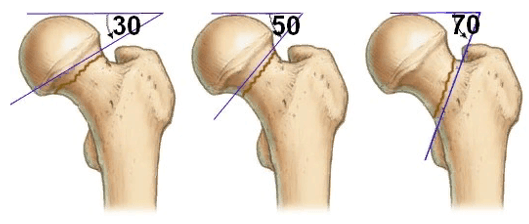

В ортопедии и травматологии используют несколько классификаций переломов шейки бедра. Разные виды переломов имеют совершенно различный прогноз. К примеру, у людей младше 50 лет трансцервикальные переломы с углом менее 30 градусов срастаются относительно хорошо. У лиц более старшей возрастной категории субкапитальные повреждения и переломы с углом более 50 градусов срастаются крайне тяжело и имеют неблагоприятный прогноз.

Слева-направо: субкапитальный, трансцервикальный, базисцервикальный переломы.

- Субкапитальный. Располагается на границе между головкой и шейкой бедренной кости. Наименее благоприятный прогноз.

- Трансцервикальный. Локализуется в наиболее уязвимом месте - в области шейки бедренной кости.

- Базисцервикальный. Находится в месте соединения шейки с телом бедренной кости. Срастается намного лучше, чем предыдущие два варианта.

Большое прогностическое значение имеет угол слома. При вертикальном положении существует большой риск смещения с последующим нарушением кровообращения в тканях бедренной кости. Такие переломы имеют наиболее неблагоприятный прогноз.